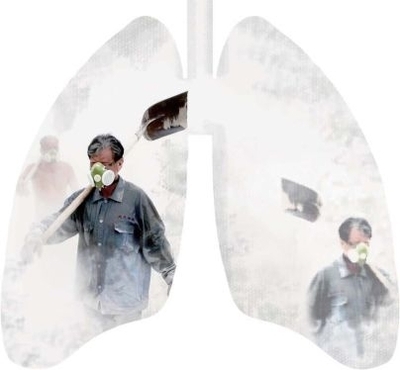

你(nǐ)还(hái)抱着侥幸心理(lǐ)?一文解答工作多久(jiǔ)可能患(huàn)尘肺病

近年来,由于国家政策的重视(shì)及(jí)社(shè)会各界的爱心关注(zhù),“尘肺病”逐渐进入大众视野(yě),越(yuè)来越多的人(rén)了解到(dào)尘肺病(bìng),也有很(hěn)多人认为这就是(shì)“穷病”,他们(men)一边谈尘肺色(sè)变,一边又迫于生计压力(lì)心存侥(yáo)幸,祈祷自己是那个例外。

尘肺病,学名为(wéi)肺尘埃沉着病,是存在(zài)严重(chóng)致死率的(de)头号职业病。由于职业原因,从事建筑、煤矿等接触大量粉(fěn)尘(chén)行业的工(gōng)人长期吸(xī)入生产性粉(fěn)尘,导(dǎo)致肺部粉尘(chén)潴留,引发肺组织弥漫性纤维化,若粉尘中的二氧化硅(guī)含量越高(gāo),则发病时间就越急促,病(bìng)变也更严重。